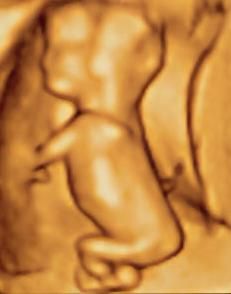

수정 후 9주부터 인간의 태아기가 시작된다.[7] 이 시기의 태아는 머리에서 엉덩이까지 약 30mm이며, 무게는 약 8g이다.[7] 머리가 태아 크기의 거의 절반을 차지한다.[8] 폐 발달을 자극하기 위해 태아는 호흡과 유사한 움직임을 보인다.[9] 심장, 손, 발, 뇌 등 주요 장기는 존재하지만 발달 초기 단계로 기능은 미미하다.[10][11] 근육, 뇌 통로가 발달하면서 제어되지 않는 움직임과 경련이 발생한다.[12]

초임부(임신 첫 경험)는 대개 임신 21주경에 태동을 느낀다.[13] 임신 5개월 말 태아의 크기는 약 20cm이다.[13]

체지방량이 급격히 증가한다. 폐는 완전히 성숙되지 않는다. 감각 피질과 시상 사이의 신경 연결은 임신 24주부터 발달하지만, 기능의 첫 번째 증거는 약 30주가 되어서야 나타난다. 뼈는 완전히 발달했지만 여전히 부드럽고 유연하다. 철, 칼슘, 인의 양이 증가한다. 손톱이 손가락 끝까지 자란다. 솜털 또는 잔털이 사라지기 시작하여 팔 위쪽과 어깨를 제외하고는 모두 사라진다. 남녀 모두 작은 유선이 존재한다. 머리카락은 굵고 숱이 많아진다. 출산이 임박하며 수정 후 약 38주에 발생한다. 태아는 자궁 밖 생활에 충분히 발달하는 임신 37주에서 40주 사이에 만삭으로 간주된다.[14][15] 출생 시 신장은 48cm에서 53cm일 수 있다. 출생 시 움직임 제어는 제한적이며, 의도적인 자발적 움직임은 사춘기까지 계속 발달한다.[16][17]